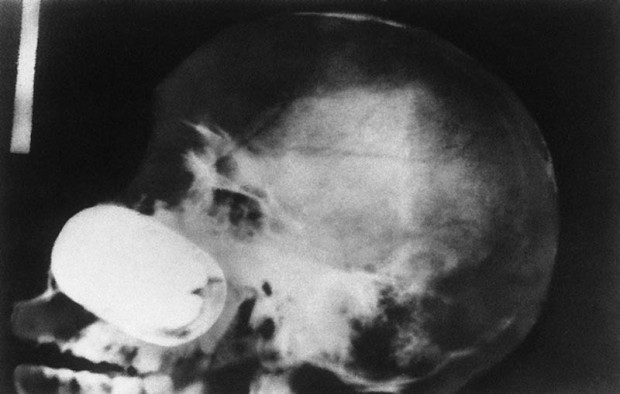

1. Череп китайца, которому в голову выстрелили пневматическим молотком.